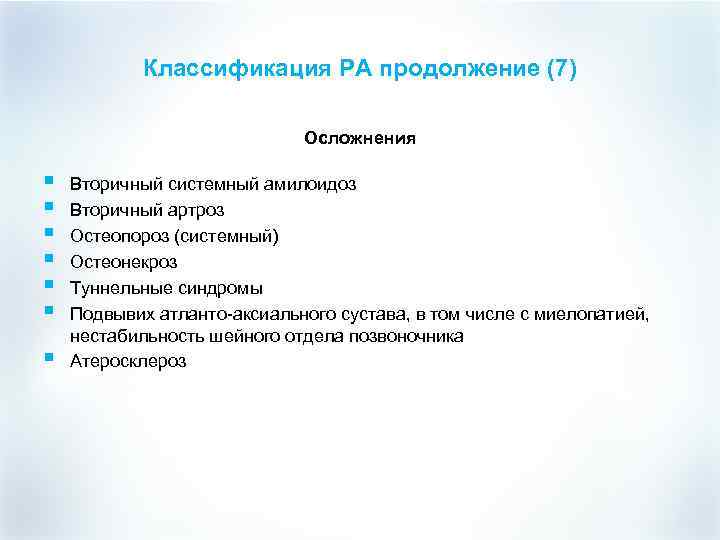

Классификация РА продолжение (7) Осложнения § § § § Вторичный системный амилоидоз Вторичный артроз Остеопороз (системный) Остеонекроз Туннельные синдромы Подвывих атланто-аксиального сустава, в том числе с миелопатией, нестабильность шейного отдела позвоночника Атеросклероз

Классификация РА продолжение (7) Осложнения § § § § Вторичный системный амилоидоз Вторичный артроз Остеопороз (системный) Остеонекроз Туннельные синдромы Подвывих атланто-аксиального сустава, в том числе с миелопатией, нестабильность шейного отдела позвоночника Атеросклероз